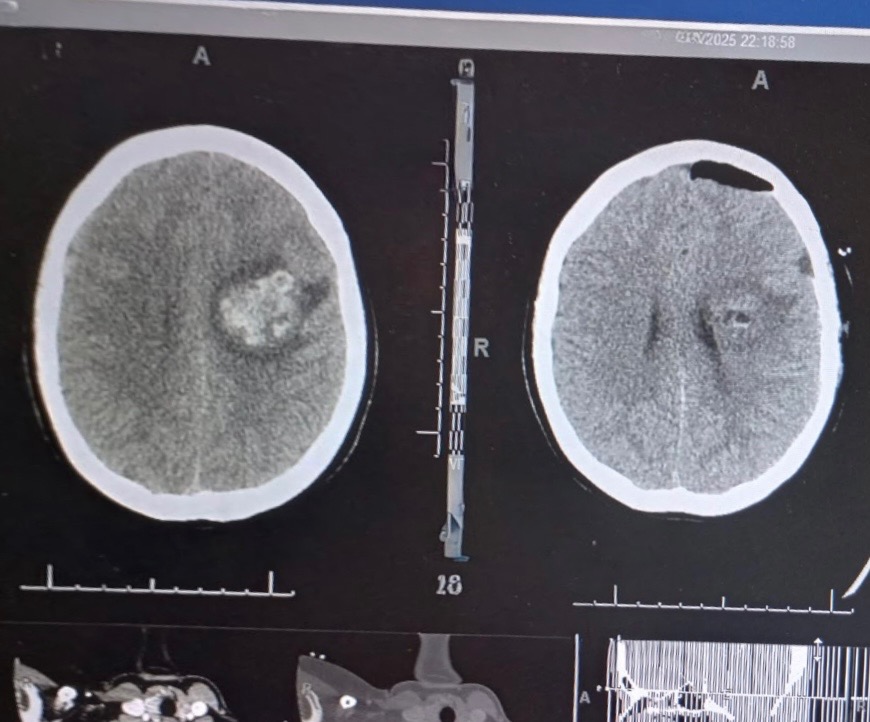

On 6/11/25 Serenity was taken to Butler hospital, where she had a CT scan done, and they found a mass on her brain along with bleeding. She was then transferred to Presby by ambulance, where they ran tests all day and discovered that she had a hemorrhaging stroke, with all the stroke symptoms on her right side. This was caused by her brain being swollen and a mass pushing on the vessels in her brain. The bleeding in the brain has resolved and right now there is no active bleed. So, now… it’s just a waiting game. Serenity was discharged from Presby on 6/13/25 with no answers. (Trust me, we fought that) but what we do know, is there is a build up of blood around the mass and we need it to absorb before they can do any further testing. And in order for the blood to absorb, we just need time. They did give her a steroid shot and that helped with the swelling of the brain and we do know that the mass in her brain is not growing at a fast pace (thank god for that!)

Serenity ultimately made the decision to go to the ER that night at midnight. They did a CT scan, MRI and also an Angiogram. On the scans they found that the mass was larger than it was previously when she was admitted a week and a half ago.

They scheduled a craniotomy for the same day, Monday 6/23/25; for this procedure, Seren was on a breathing machine.. they removed part of her skull and made a half dollar sized opening that they can go in and evacuate the access blood around the mass. After the blood was removed, they did more testing to get a better image of the mass. It turns out, the mass was several vessels that were bleeding periodically, or bleed, stop, then bleed again, for who knows how long. Probably years. That were considered a cavernous malformation and it was sent away to get biopsies! They hope they were able to remove and fix, all the vessels that were bleeding in her brain. She is going to have follow up testing this week to view where the mass was and to see if there is any access vessels there that they may have missed. The doctors stated that this is something that she was probably born with.